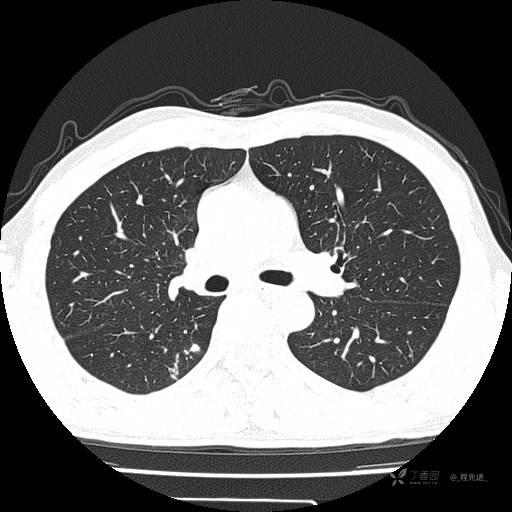

2月特别精彩病例|咳嗽、咳痰20余天,典型病例分享【结果已公布】

呱呱叫了 等 2 位达人已点赞患者性别:男

患者年龄:51岁

主诉:咳嗽、咳痰20余天

简要病史:20余天前开始出现咳嗽、咳痰症状,阵发性刺激性咳,白色粘痰,不易咳出,无发热,无咯血,无恶心、呕吐等不适,未诊治,咳嗽、咳痰症状持续存在。

体格检查:T:36.3 ℃ P:79 次/分 R:20 次/分 BP:128/64 mmHg,神志清楚,呼吸平稳,双肺呼吸音粗,右下肺闻及细湿性啰音。心率79次/分,节律整齐,各瓣膜听诊区未闻及病理性杂音。腹部未见异常,双下肢无水肿。

辅助检查:我院门诊胸部CT示:如下。心电图:窦性心律;正常心电图。